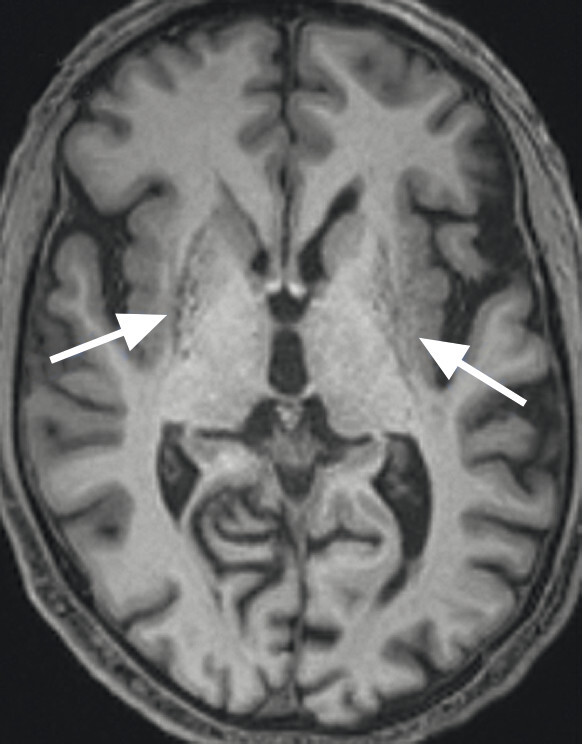

- Der Nachweis der Degeneration des dopaminproduzierenden Nigrosoms 1 innerhalb der Substantia nigra und des damit verbundenen Verlusts des Schwalbenschwanzzeichens (Swallow Tail Sign; Abb. 69.2) zeigt keinen eindeutigen Mehrwert in Bezug auf Diagnose und Differenzialdiagnose von Parkinson-Syndromen. Die Beurteilung des Schwalbenschwanzzeichens ist nämlich deutlich scanner- und befunderabhängig und wird in bis zu 50% der Fälle auch bei Patientinnen und Patienten mit frontotemporaler Demenz und Alzheimer-Demenz als anomal eingestuft [12].

Abb. 69.2 Parkinson-Syndrome.

a Schwalbenschwanzzeichen beidseits als Ausdruck eines unauffälligen dopaminproduzierenden Nigrosoms 1 (Pfeile).

b Beim idiopathischen Parkinson-Syndrom, aber auch bei anderen neurodegenerativen Erkrankungen, ist das Schwalbenschwanzzeichen (Swallow Tail Sign) in der SWI-MRT (Schichtdicke 2 mm) einseitig oder beidseitig nicht abgrenzbar (Pfeile).